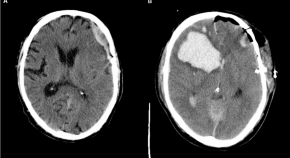

Cheng et al. developed a computer vision tool (SeeMe) that detects low-amplitude facial movements in comatose brain injury patients. Purposeful responses are detected days before clinical detection, suggesting that covert consciousness may often go unrecognized.